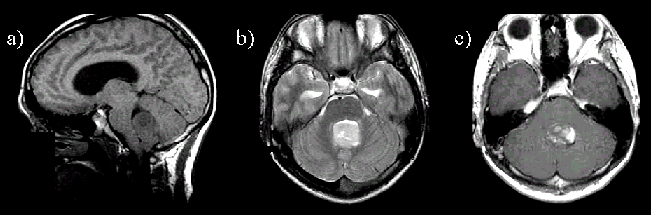

② 영상 검사

- MRI(자기공명영상): 가장 정확하게 뇌 구조와 종양을 확인할 수 있습니다.

- CT(전산화 단층촬영): 급성 상황이나 출혈 여부를 확인하는 데 유용합니다.